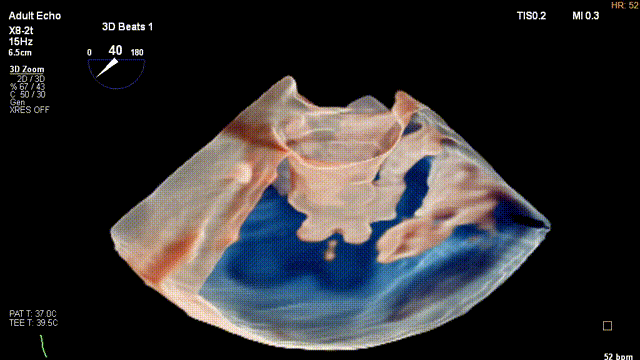

新近推出的光源心腔镜、透视心腔镜及彩色心腔镜等成像功能,让心脏结构及组织的毗邻关系显示更清晰。“更重要的是,新的成像功能可以同步显示心脏组织结构和心腔内血流信号,使我们能够在器械植入、瓣膜修复或置换时,更加快速和精准地评估介入手术效果,患者术后并发症风险也会随之降低。在左心耳领域,使用TrueVue Glass能够观察到左心耳结构的形态和铸型,对临床很有意义。从目前的一个资料和数据来看,超声在该领域亦拥有取代CT的发展潜力。”

TrueVue Glass显示左心耳分叶及铸型